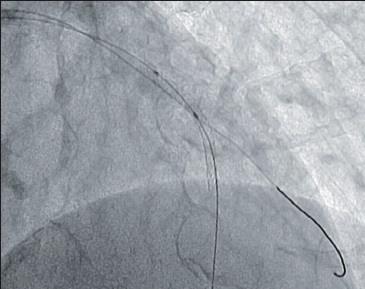

Програмне забезпечення 3D Roadmap

Флюороскопія в реальному масштабі часу накладається на об’ємні 3D зображення, що були отримані під час 3D ангіографії. При русі столу під час роботи в режимі 3D Roadmap автоматично відбувається співставлення зображення 3D та флюороскопічного. Всі рухи системи пов’язані з накладанням 3D об’єму та скопічних зображень, включаючи зміну кута нахилу С-арки, SID, розміру поля огляду, висоти позиціонування столу. Можливим є зсув попіксельно вручну для більш точного співставлення об’єму та флюоро.